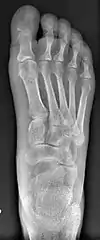

- For severe bunion deformity correction (Fig. 7)